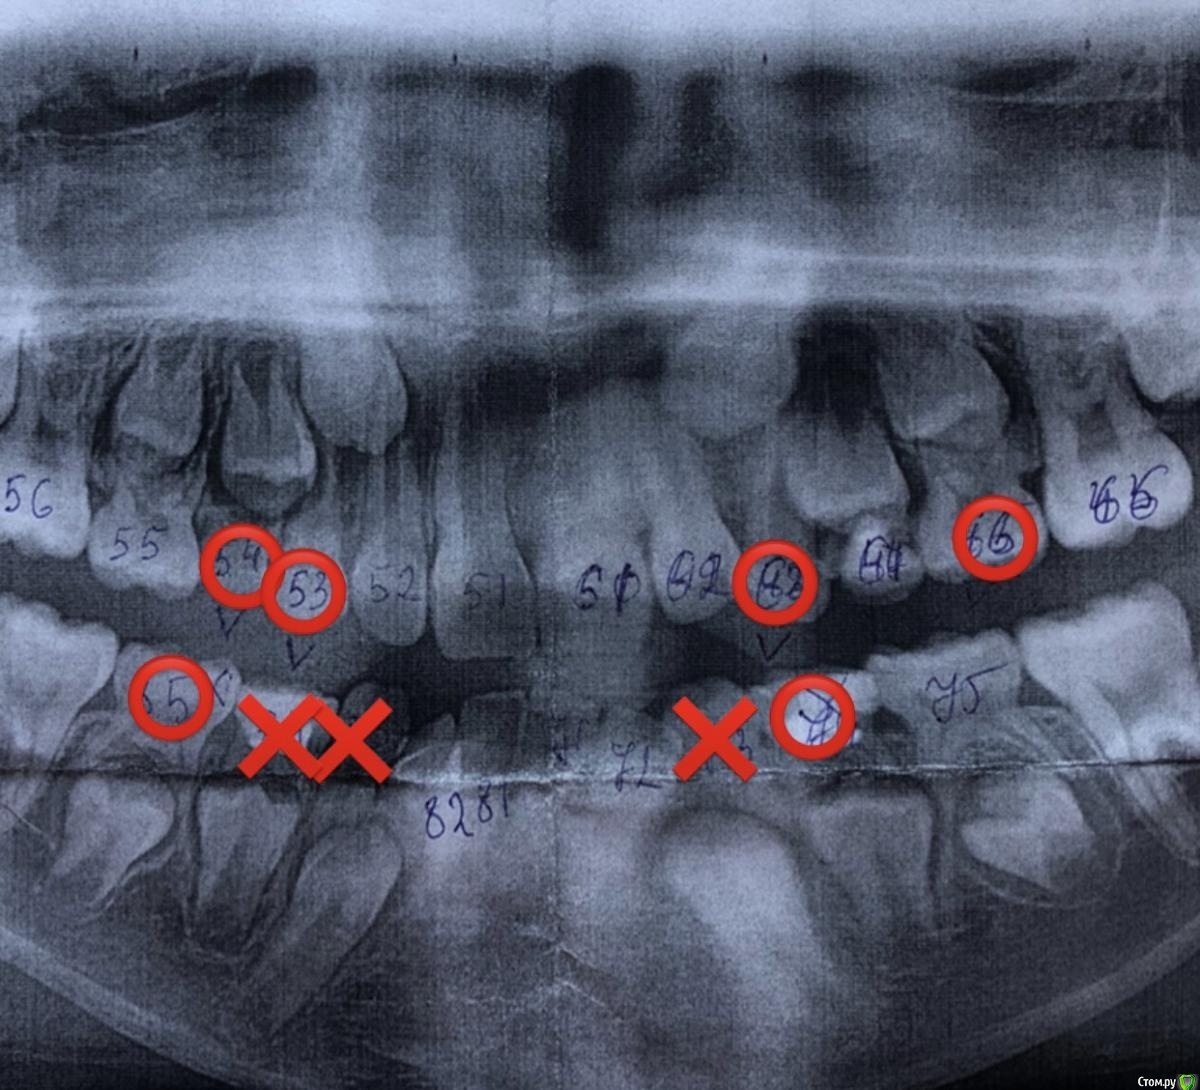

GalinaE Опубликовано 5 октября, 2020 Поделиться Опубликовано 5 октября, 2020 Нам 9 лет. Передние зубы выросли криво ввиду недостатка места. Ортодонт из поликлиники дал указание носить пластину, чтобы расширить челюсть. За 3 месяца носки у дочери внизу выпало 2 зуба, врач ушла в декрет. Пошли платно. Новый доктор сказал, что пластины не нужны и назначил ужалить 6!!! зубов. Я немного в шоке, это с учётом того, что сейчас внизу трёх уже нет, но уже растут. Допустим такой подход?На снимке, сделанном в начале лечения, крестиком отмечены выпавшие зубы. Кружочком - те, которые нужно удалить Ссылка на комментарий

Rania Опубликовано 5 октября, 2020 Поделиться Опубликовано 5 октября, 2020 Здравствуйте. У зубов, которые рекомендовали удалять, корни резорбированы. Поэтому удалите Вы их или нет, они и так сами скоро выпадут. В 9 лет еще нет такой острой необходимости удалять молочные. Хорошо следите за гигиеной, побольше жевательной нагрузки ввиде яблок и морковки и проверить пластинку у другого ортодонта не дожидаясь Вашего врача из декрета. 1 Ссылка на комментарий